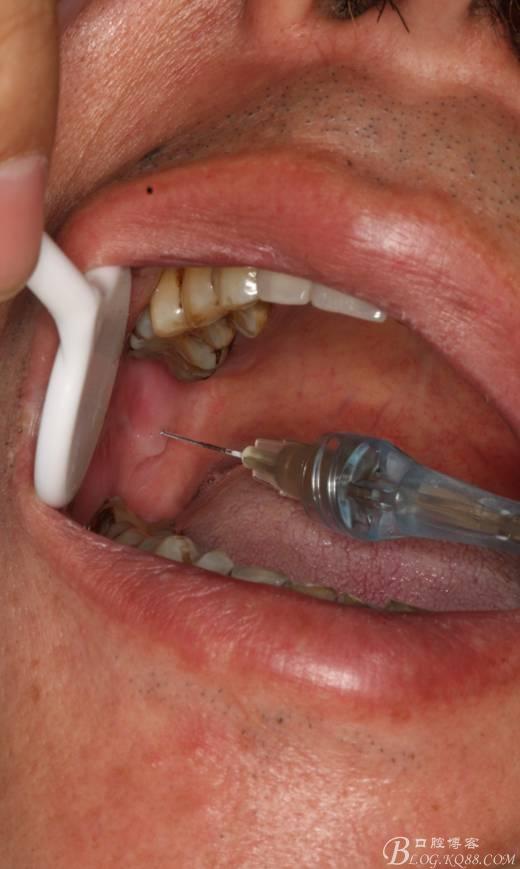

1.麻醉